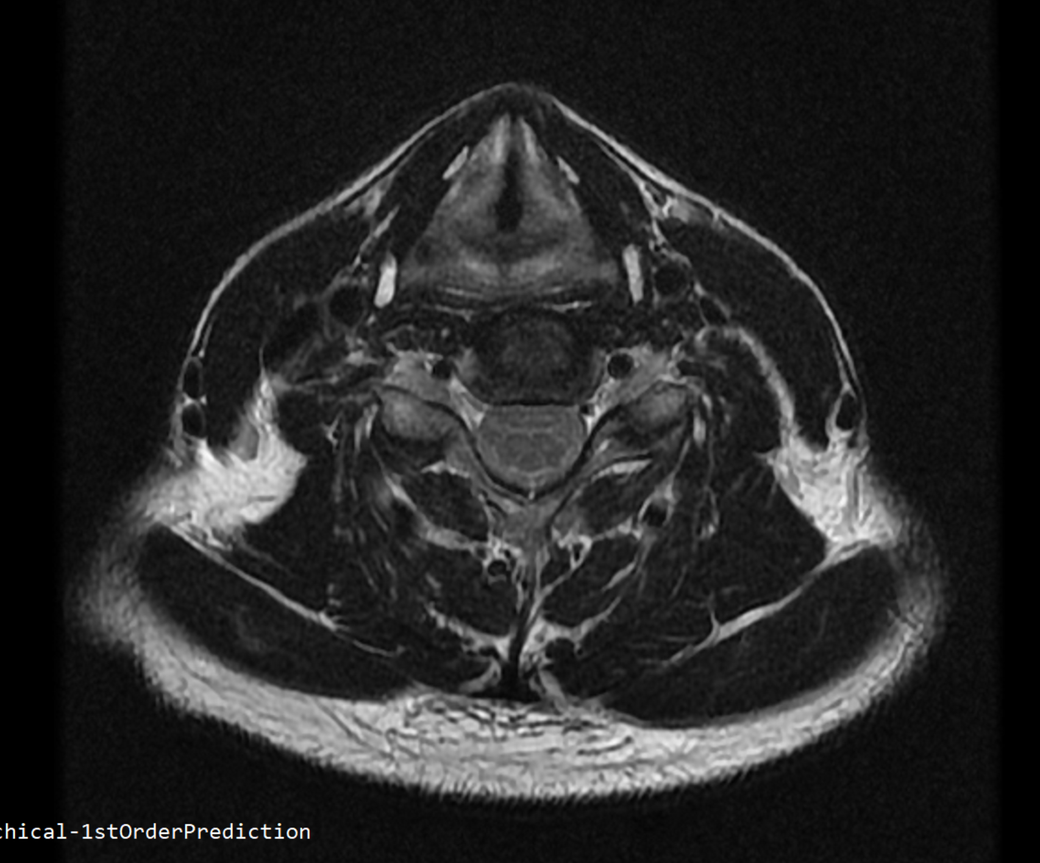

안녕하세요 목 경추 상단부터 순서대로 mri 촬영인데요

전체적으로 봐주시면 감사하겠습니다

• 2번 째 사진